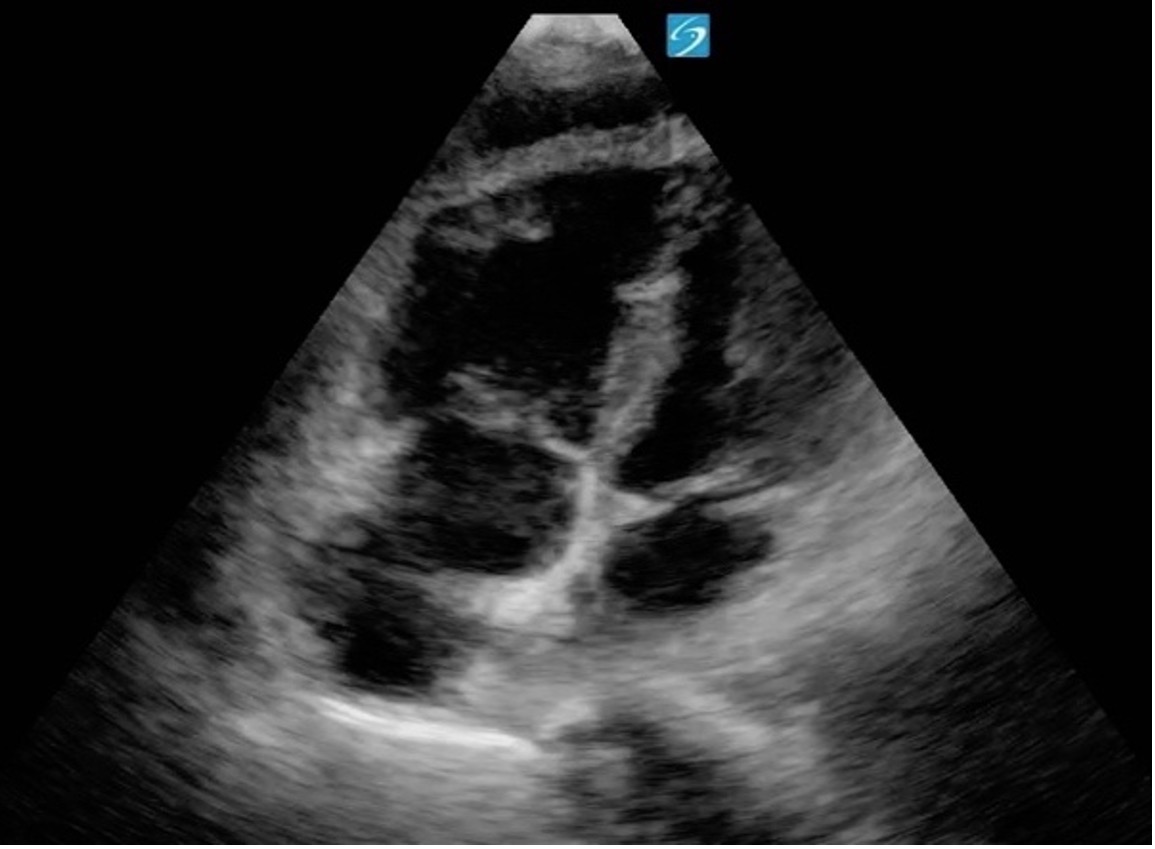

In A4C view, you can assess LV wall motion at the basal, mid, and apical levels of the inferoseptal and anterolateral walls (figure 19). This view is also useful for visual estimation of overall contractility and evaluation of the LV’s size and shape throughout systole and diastole.

It is important to avoid foreshortening in the A4C view, as this can underestimate LV length and overestimate function. If the LV appears round or blunt at the apex, the image is likely foreshortened—slide the probe laterally and slightly inferiorly to better align with the cardiac apex, and angle it more anteriorly (toward the face) to bring the true apex into view and ensure a full-length chamber.

Formal echocardiography uses apical views to calculate EF using Simpson’s biplane methods; however, this is beyond the scope of PoCUS practice

Figure 19: Apical 4 Chamber view in cardiology convention with the labeled left ventricular walls